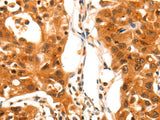

Applications WB,  IHC

IHC 1:100-1:300